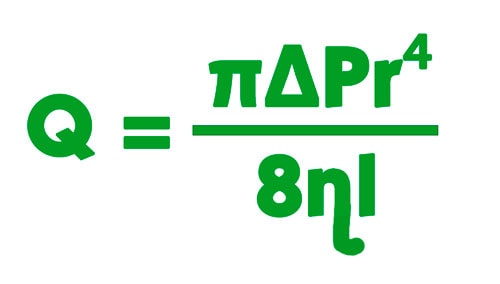

Según la ley de Poiseuille, el flujo (Q) está relacionado con:

- la diferencia de presión (ΔP) a cada extremo de cilindro en el cual pasa el fluido

- el radio del cilindro (r)

- la longitud del cilindro (l)

- la viscosidad (ɳ) del fluido.

Aplicando la ley a un catéter, el flujo aumenta si la diferencia de presión aumenta y/o si el diámetro es más grande. Por otra parte, el flujo disminuye si la longitud del catéter es más grande y si el fluido que pasa en su interior es más viscoso.